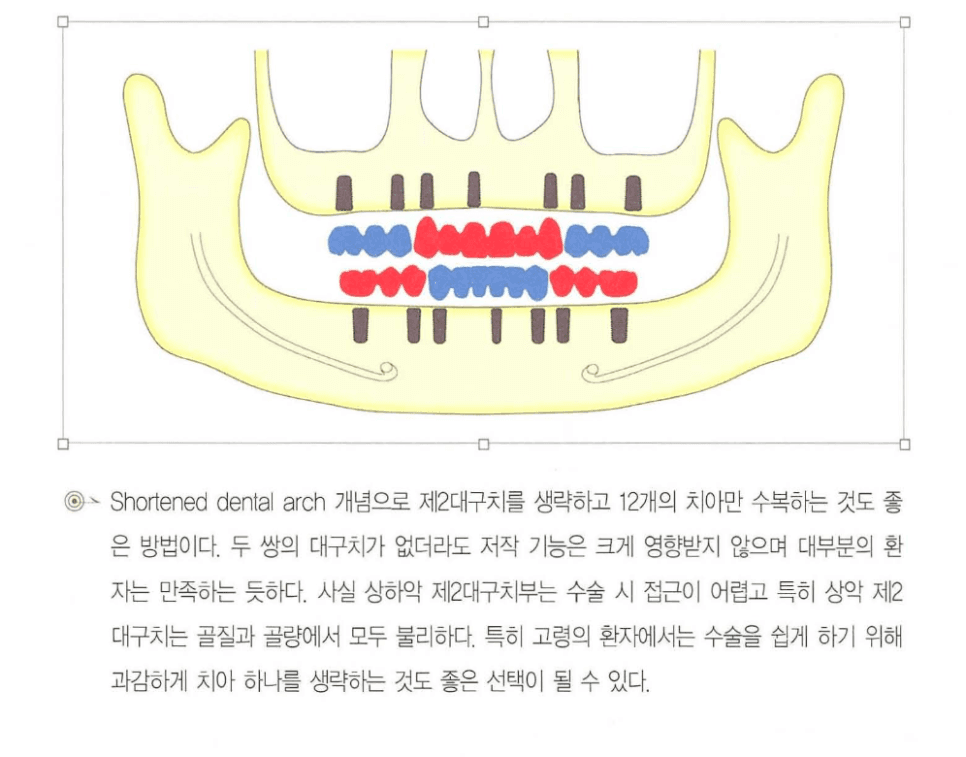

단축 치열궁(Shortened Dental Arch)

제2대구치까지 수복하지 않고 제1대구치까지만 수복하는 개념입니다. 양측 5~7개 치아, 즉 구치 6개 접촉만 유지되어도 저작 효율은 크게 저하되지 않는다는 것이 다수의 임상 연구에서 보고되어 있으며, 특히 고령 환자에서는 수술 난이도와 합병증 위험을 함께 낮추는 합리적 선택이 됩니다.

“전부 심어야 한다”는 고정관념 대신, 얻는 것(교합 효율)과 치르는 비용(합병증 위험)을 비교해 과감히 제2대구치를 생략하는 것도 좋은 전략입니다.

[그림 6] 단축 치열궁 개념을 적용해 제2대구치를 생략하고 상·하악 각 12개 치아를 수복하는 설계 예시.